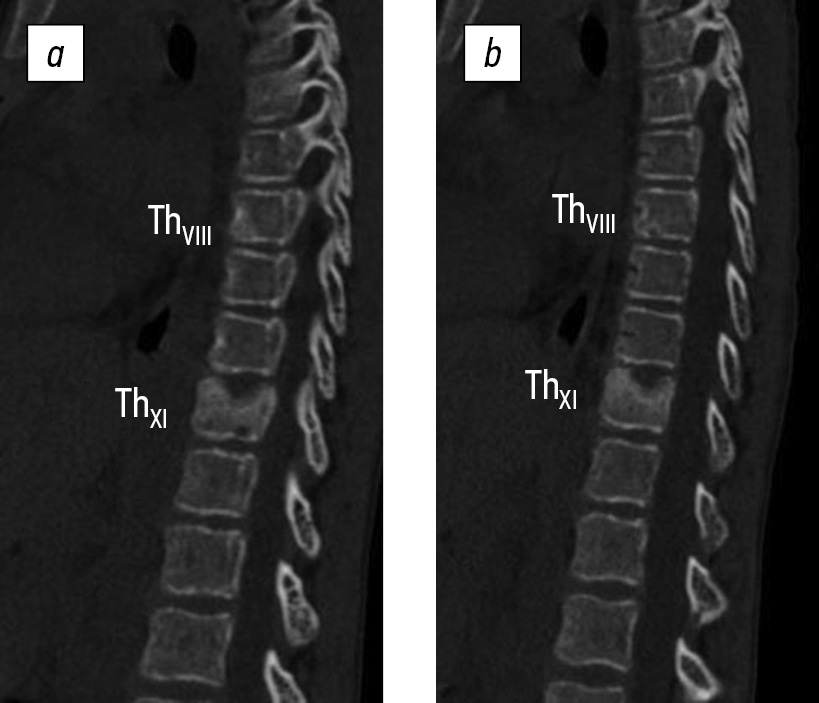

CT findings: A defect with a niche shape measuring 13 × 17 × 7 mm was detected in the middle section of the ThXI vertebral body. The defect destroyed the cranial closure plate and had indistinct, uneven sclerosed contours, and reactive osteosclerosis. In addition, an area of subchondral lucency measuring 4 × 6 mm was found at the cauda terminal plate on the posterior left surface, which caused thinning of the adjacent cortical layer. A homogeneous increase in the densitometric density of the osteosclerosis type was detected in the anterior part of the ThVIII vertebral body, measuring 12 × 8 mm, with a vaguely delineated area of the subchondral lumen of the caudal closure plate up to 4 × 6 mm. In addition, the height of the intervertebral spaces of ThX–ThXI and ThVIII–ThIX decreased. The facet joints at these levels were indistinct. The spinal canal does not exhibit any features. Compared with the previous study of the CT archive, negative dynamics were observed because of the progression of destruction of the ThXI vertebral body and the appearance of new zones of osteolytic changes in the ThVIII and ThXI vertebrae (Fig. 2). CT of the thoracic cavity showed no pathologies.

Fig. 2. Computed tomography of the thoracolumbar spine showing signs of destructive changes in the ThVIII and ThXI vertebral bodies 3 months after disease onset